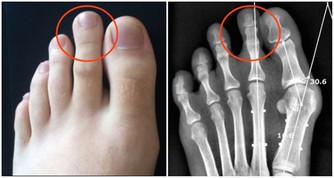

6. 你注意到手、唇和腳變大甚至變形

在許多低鈉血症病例中,人們的手、唇、腳都會出現明顯的腫脹或變色。當整個身體的所有細胞都膨脹時,皮膚也會開始明顯膨脹。由於腫脹和血液中過量的水分,你可能會突然體重增加。如果你每天喝10杯以上的水,並註意到手部、嘴唇和腳部腫脹或變色,請考慮減少飲水量並查看症狀是否消退。